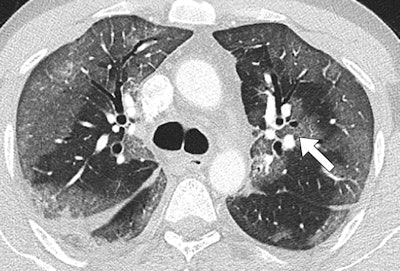

Patients hospitalized with MERS most commonly showed bilateral predominantly subpleural and basilar airspace changes, with extensive ground-glass opacities and less consolidation, concluded the study team from King Abdulaziz University Hospital in Jeddah. The subpleural and peribronchovascular nature of most of the abnormalities is suggestive of an organizing pneumonia pattern, they wrote.

The images showed that airspace opacities were more common than interstitial changes, according to the authors. Five patients had both ground-glass opacities and consolidation -- with ground-glass opacities being more extensive in all but one of those patients. One patient had only ground-glass opacities and another had isolated consolidation.

The radiologists found smooth septal thickening in three of the seven patients, and minimal peripheral reticulation, traction bronchiectasis, and perilobular opacities were found in just one patient. None of the patients had tree-in-bud pattern, cavitation, or intrathoracic lymph-node enlargement, the authors wrote.

The most common CT finding in hospitalized patients with MERS is bilateral predominantly subpleural and basilar airspace changes, with more extensive ground-glass opacities than consolidation, Ajlan and colleagues concluded.

"The predilection of the abnormalities to the subpleural and peribronchovascular regions is suggestive of an organizing pneumonia pattern," they wrote. "Recognizing this pattern in acutely ill patients living in or traveling from endemic areas may help in the early diagnosis of MERS-CoV infection."